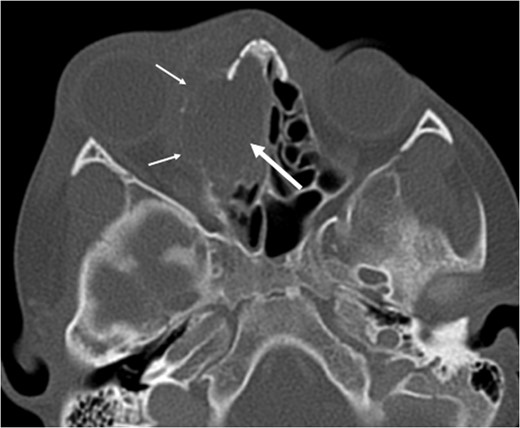

A 6-year-old boy with a background of asthma presented to a tertiary paediatric unit in May 2016 with a 3-day history of right eye pain, proptosis and erythema under the care of the ENT team. A provisional diagnosis of a periorbital cellulitis was made secondary to ethmoid sinusitis and management with intravenous antibiotics (ceftriaxone), intranasal steroids, saline douches and topical oxyxlometazoline was initiated. Ophthalmological assessment demonstrated normal colour vision, acuity and light reflexes bilaterally but also proptosis-related ophthalmoplegia. Computed tomography (CT) imaging of the orbits and paranasal sinuses demonstrated complete opacification of the right-sided paranasal sinuses and compromise of the right frontal and ostiomeatal unit. In addition there was an expansile abnormality centred on the ethmoidal labyrinth with bony remodelling of the lamina papyracea and a subperiosteal collection adjacent to the medial orbital wall (Figs 1 and 2). The most likely diagnosis was felt to be an infective process with mucopyocele formation complicated by a subperisoteal post-septal collection. An MRI scan with gadolinium of the orbits and sinuses confirmed the unilateral pattern of sinus opacification within the right frontal, ethmoids and maxillary sinus. The lesion demonstrated multiple fluid–fluid levels and peripheral enhancement (Figs 3 and 4). The patient was treated by endoscopic drainage of the lesion, which revealed only blood. He initially had some improvement of his proptosis but recurred within a few days and so further, more extensive endoscopic debridement was performed.

Axial post-contrast CT demonstrating the peripherally enhancing right-sided intra-orbital subperiosteal component. The expansile lesion centred on the right ethmoidal labyrinth demonstrates a faint fluid–fluid level.